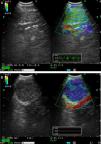

Case ReportsCase 1A 66-year-old man, former smoker for 4 years, with a history of moderate COPD and left pleural effusion and cytology negative for malignancy. In the previous 4 months, he had 2 episodes of left lower lobe (LLL) pneumonia. He presented in the emergency room with left pleuritic pain, increased cough and poor general condition. Positron emission tomography-computed tomography (PET-CT) revealed a hypermetabolic necrotic mass in the LLL and hypermetabolic left lower paratracheal, left subcarinal-paratracheal and left para-aortic lymphadenopathies, suggestive of metastasis. Bronchoscopy was performed, showing endobronchial tumors in LLL segment 10. Bronchial brushing cytology showed squamous cell carcinoma. EBUS (BF-UC180F Olympus, Japan) was performed, with aspiration of lymph node stations 4R-1 (5.4mm), 4R-2 (5.9mm), 4R-3 (7.5mm), 7-1 (6.6mm×21.4mm), 4L-1 (13.1mm×15.4mm) and 7-2 (12.6mm×15.5mm) after a change of needle. Lymph node stations 7-1 and 7-2 were examined using elastography (EU-ME2 Premier Plus Olympus processor, Japan), obtaining a qualitative pattern of color images showing tissue areas with greater consistency in dark blue, intermediate in green and the softest in red (Fig. 1A and B). In double-screen mode, the B-mode image is on the left, and on the right, the color-coded image of stiffness responses is superimposed on the B-mode image. The region of interest for the elastography calculations was selected manually, with inclusion of the node station and adjacent tissues. Aspirates were negative for malignancy, with the exception of stations 4L-1 and 7-2, that returned a diagnosis of squamous cell carcinoma and tumor necrosis.

(A) Conventional black and white EBUS B-mode image (left) and with real-time EBUS elastography (right), showing a 6.6mm benign subcarinal lymph node, seen as an area of intermediate rigidity (green). (B) EBUS elastography (right) showing a 12.6mm malignant subcarinal lymphadenopathy, seen as a stiff area (dark blue-cyan), due to squamous cell carcinoma infiltration.